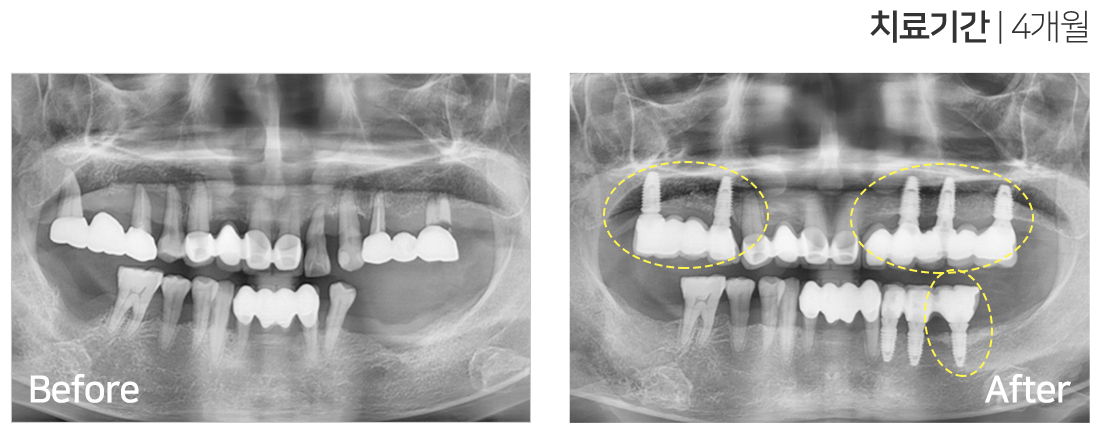

임플란트 시술 사례

IMPLANT TREATMENT CASES

※ 전신질환 및 관리 능력에 따라 임플란트 주위염 등의 부작용이 있을 수 있습니다.